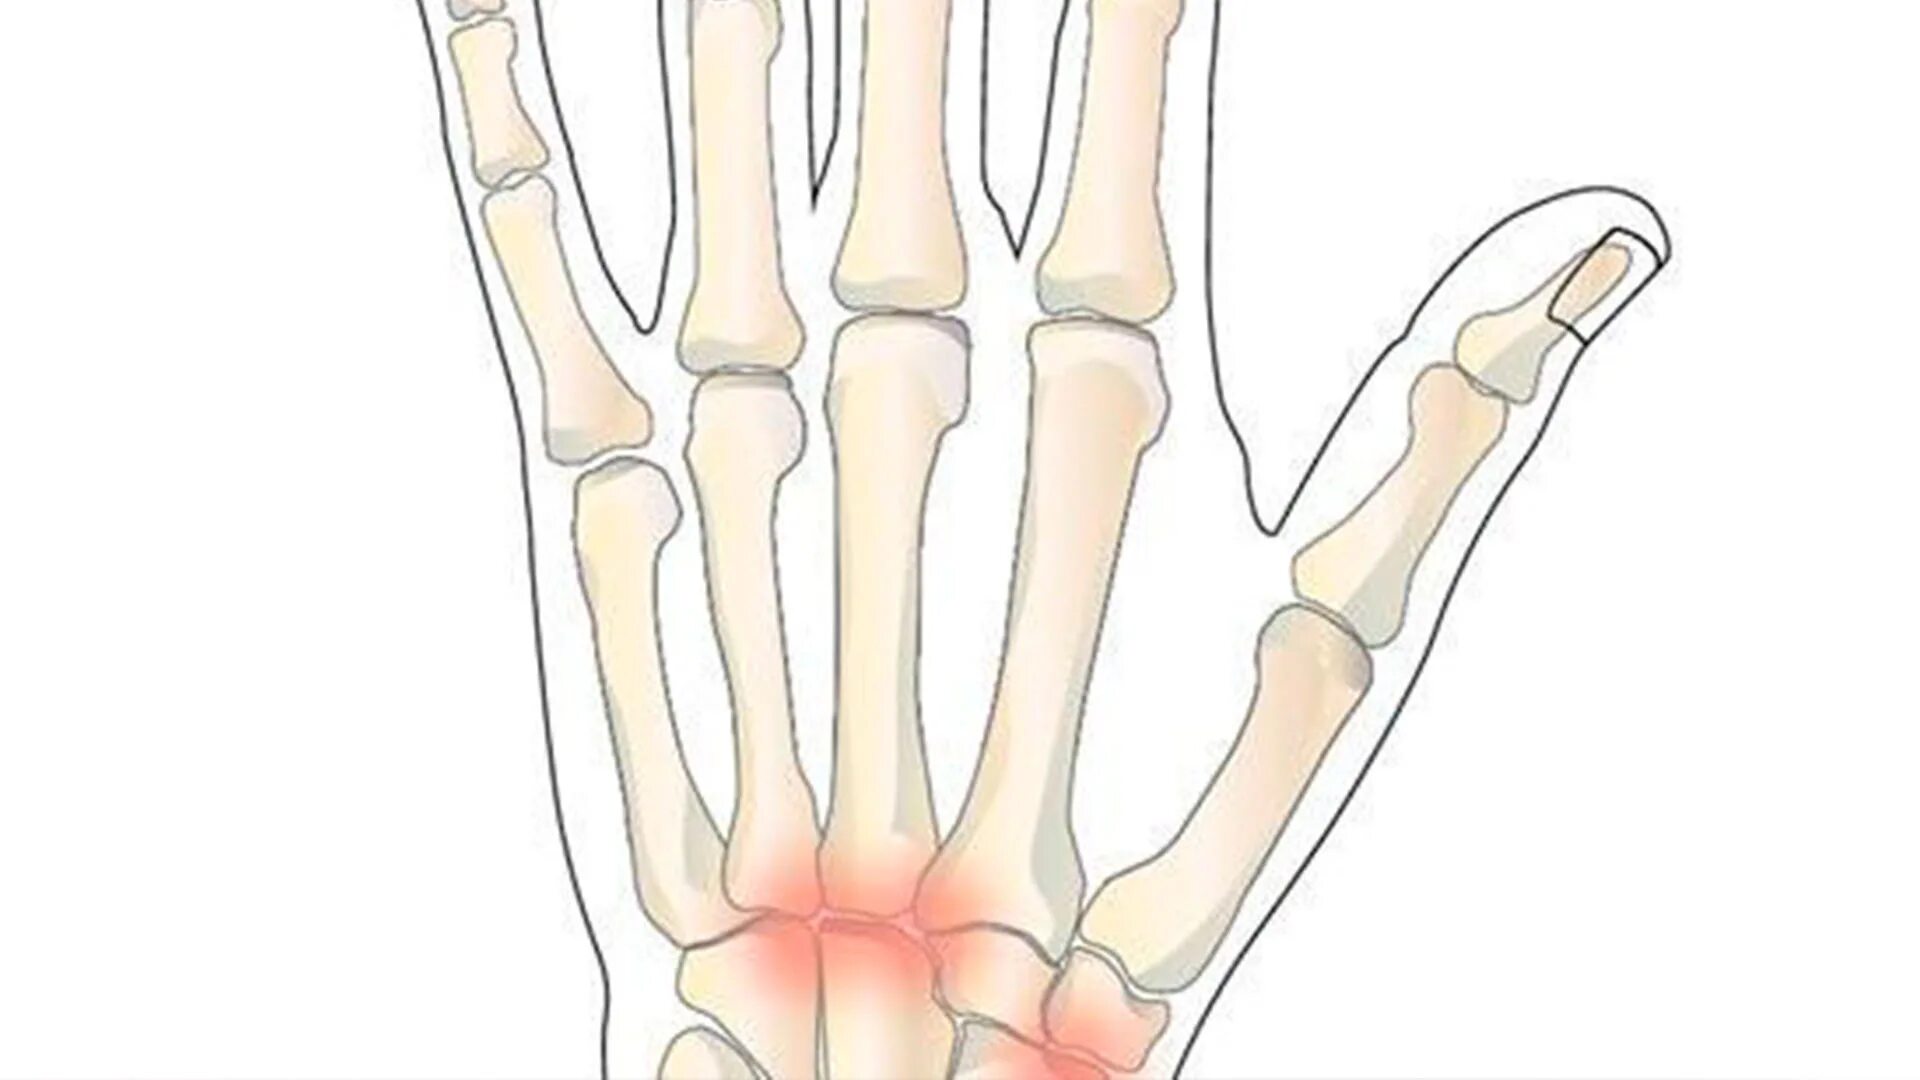

Артроз запястно пястного сустава